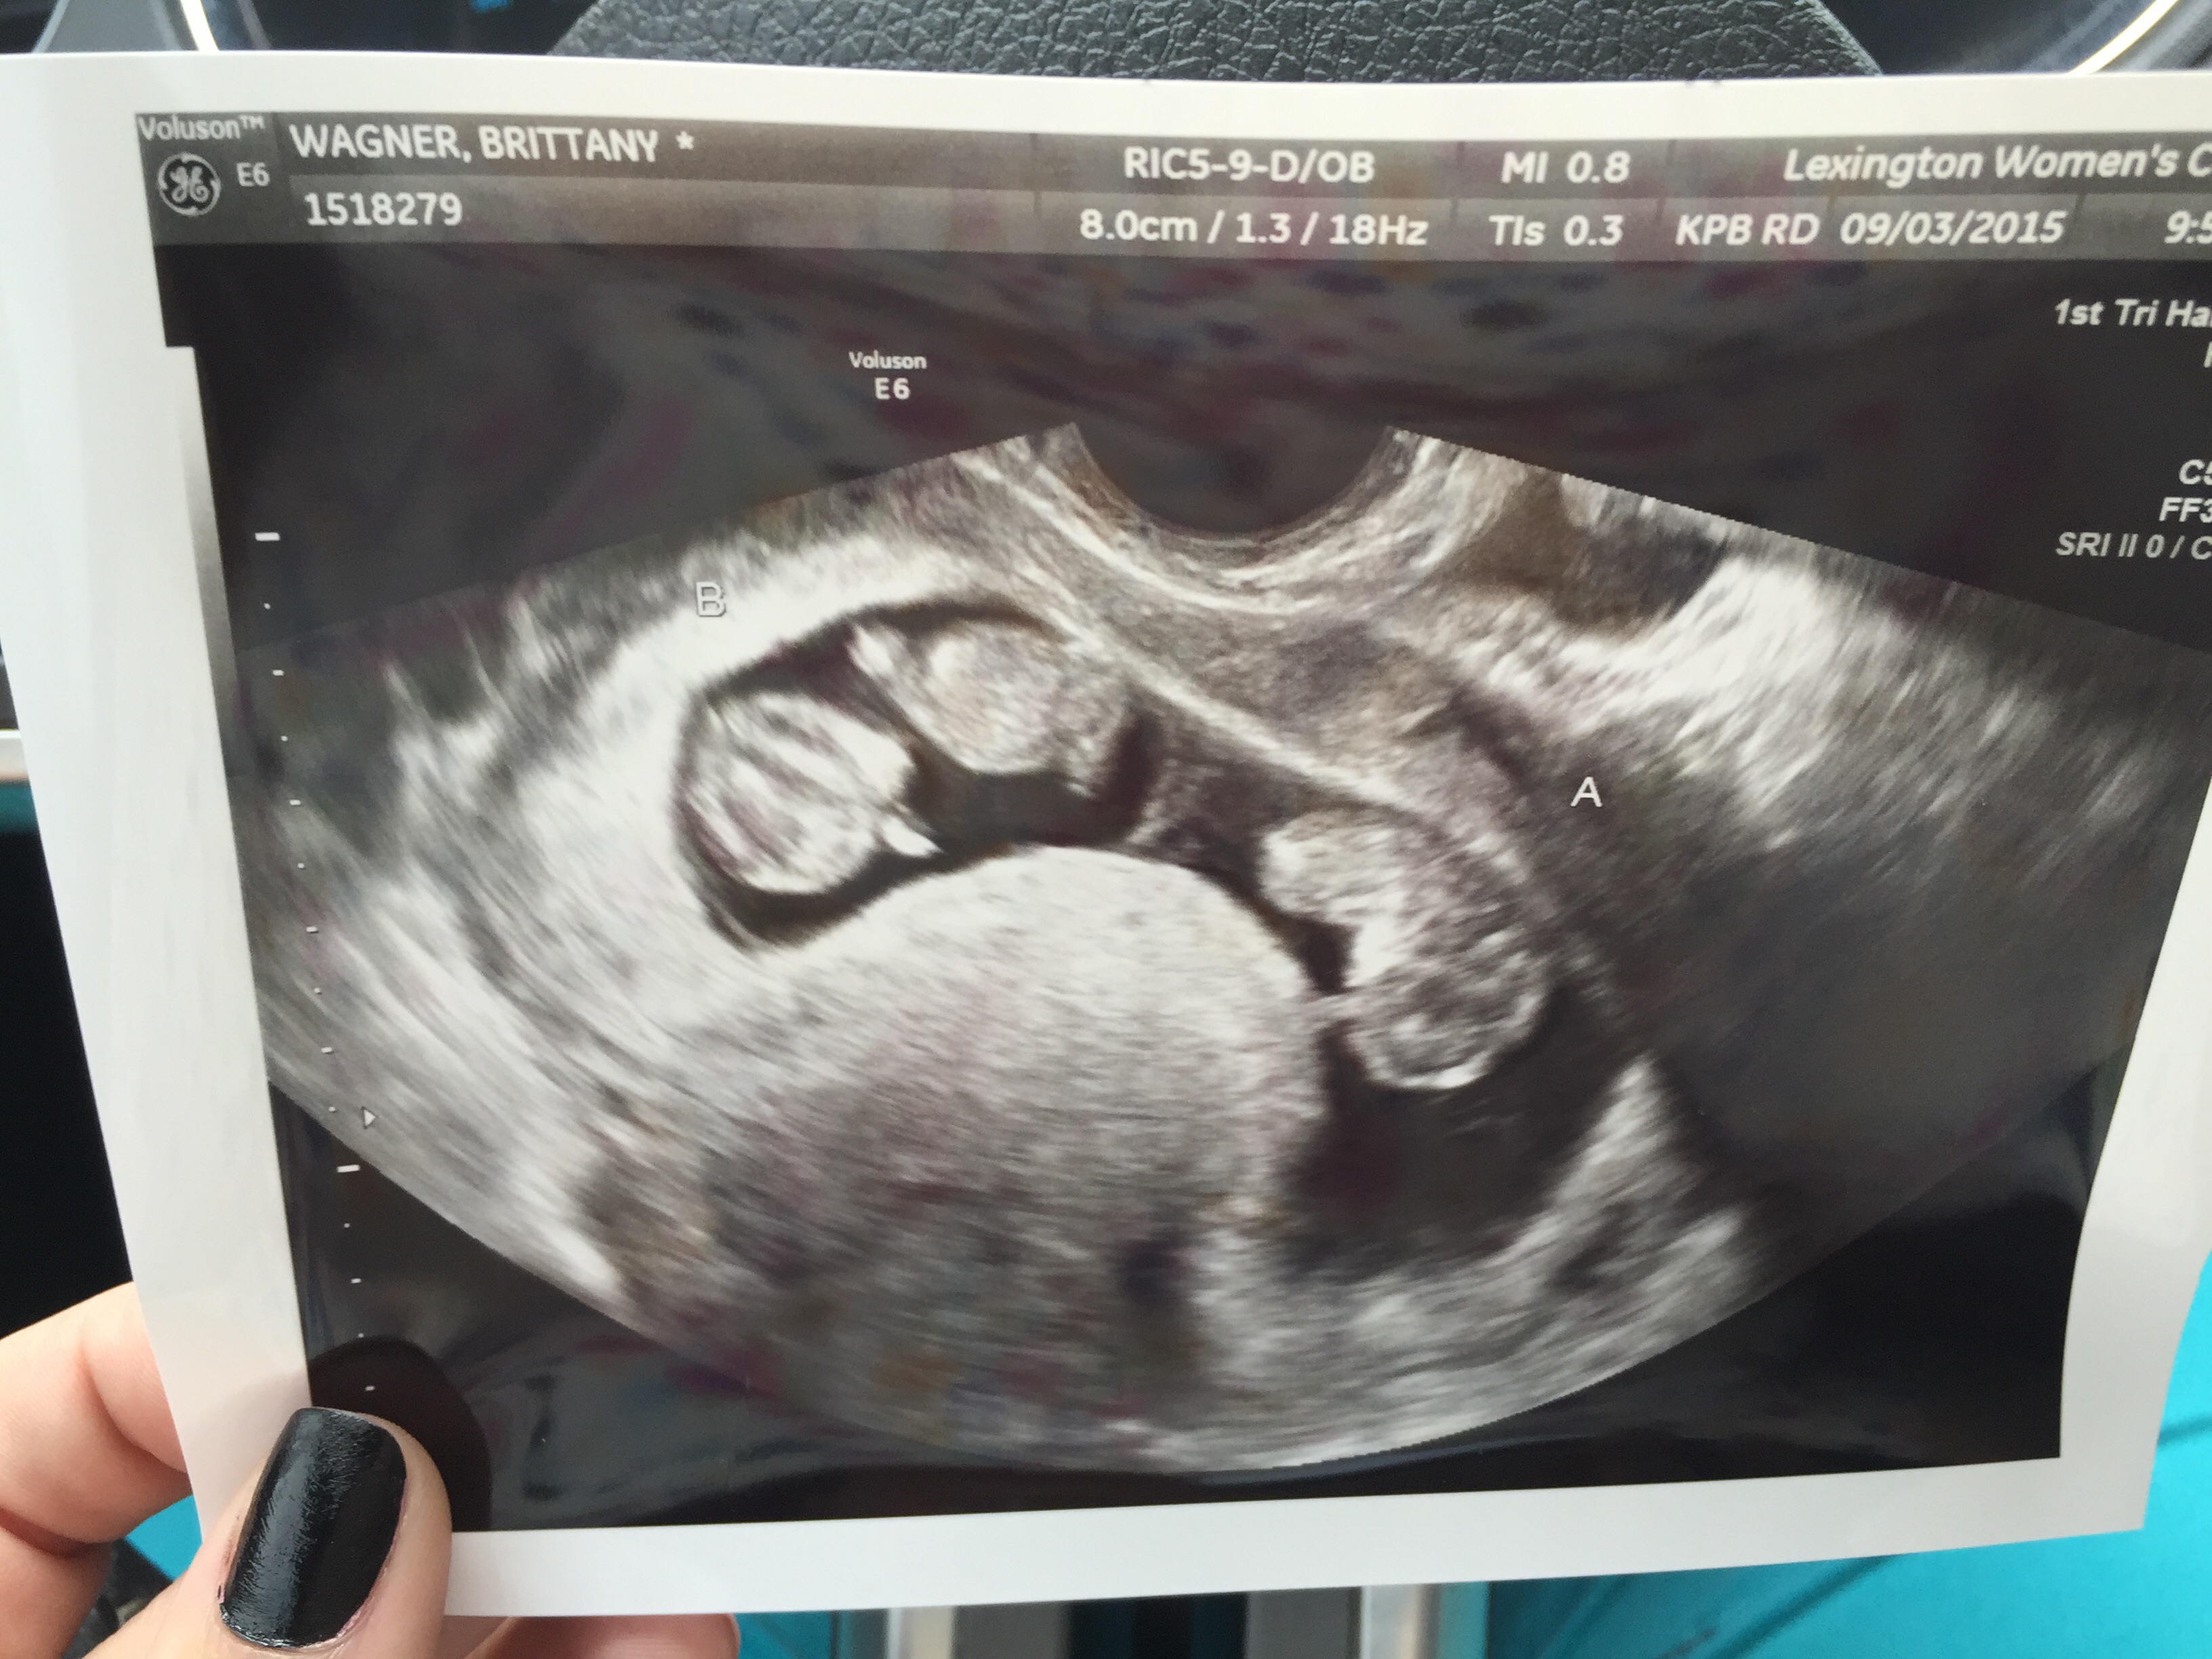

Attachment 27165Attachment 27165Attachment 27165 I feel like they are boys

Not seeing any clues. How far along are these?